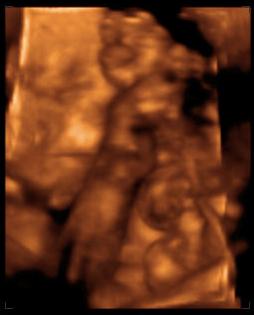

Mindjárt jönnek a 4D képek!!!

Na akkor a 4D képek! Törpike (merthogy neve még változatlanul nincs), fejecskéje 6,71 cm, súlya kb. 920 gr., 1 héttel kisebb mint a kora, így várhatóan augusztus 26-ra leszek újabb időre kiírva, nem aug. 18-ra. Talán a dokim visszaér addigra szabiról, és tudok vele egyezkedni. Szóval összességében jól alakulnak a dolgok. A 4D egyébként irtó jó volt! Most először hallottuk a szívverését is, és nem is tudom szavakba önteni, milyen különös érzés keríti hatalmába az embert ott a félhomályos vizsgálóba, amikor meglátja először a 4D képet. A kezecskéket rendesen, nem csak a csontokat belőle és a halvány körvonalakat. Az orrocskát, a szemecskéjét, még ha csukva volt is, mert a kis drága aludt végig, hiába volt előtte süti meg bármi, nem nagyon hatotta meg :) Az összes kezét, lábát végig az arca előtt tartotta szinte teljesen eltakarva azt, de azért lehetett látni is, na meg olvadozni. Egyébként medence fekvésű jelenleg, vagyis hát a vizsgálatkor, de van még bőven ideje, helye befordulni és mocorogni, úgyhogy nem aggódom. Kértem a dokit, hogy nézze meg a méhlepény-méhszáj távolságát. Kérdezte, mert hogy mélyen volt a lepény? Mondom igen, 12 mm-re. Megmérte, és képzeljétek, a távolság 6!!!!! cm-re nőtt, tehát teljesen felhúzódott, illetve nem kicsit, és már azt is írta a leletre hogy hátsó fali korban érett placenta :) Június 13-án megyek 30 hetes UH-ra a dokimhoz, majd kérem őt is hogy mérje meg, kíváncsi vagyok igazolja-e ezt, és hogy akkor nincs akadálya (legalábbis emiatt) a spontán szülésnek.

Férjecském majdnem elsírta magát a meghatottságtól a vizsgálat elején még (ezt utána mondta), és egyébként azóta is 10 centivel közlekedik a föld fölött, láthatóan eufórikus állapotban van, ami szűnni nem akar, nagyon imádnivaló :) Mondjuk ha a másik nem lenne, akkor ugyanez, de igaziból más most a kapcsolat, én is így érzem. Személyesebb lett a baba iránti szeretetünk, és amikor mentünk az UH után az utcán, olyan más volt. Mintha kivilágosodott volna minden, pedig viharos esős idő volt, és az emberek is mások lettek volna, én nem is tudom, nagyon jó érzés volt :)

Jól van, nem csigázom tovább a kíváncsiságotokat. Szerintem nem kell hozzá magyarázat, magatoktól is látni fogjátok a lényeget ;)